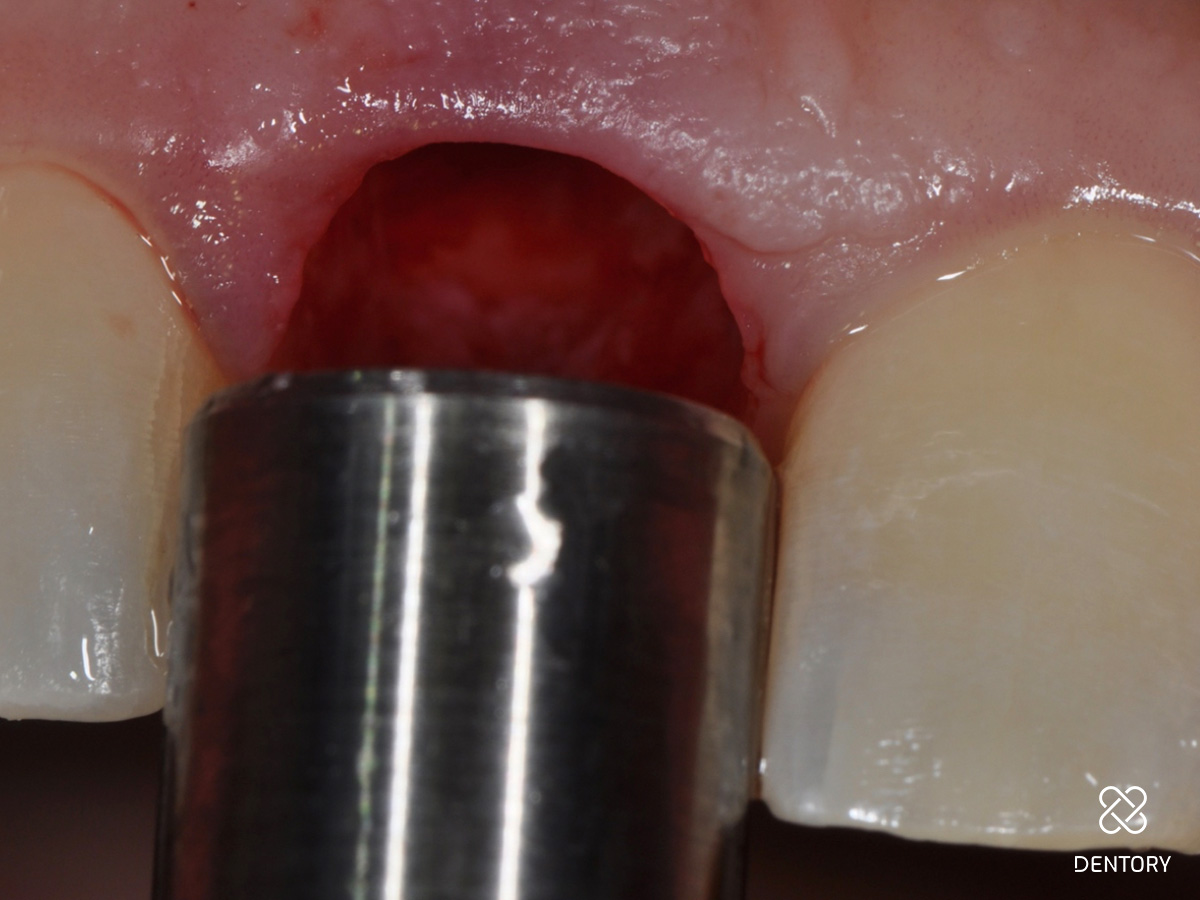

Abbildung 7

Okklusale Ansicht der Extraktionsalveole. Die Entfernung des Saumepithels erfolgt mit einem grobkörnigen Diamantbohrer.

Abbildung 8

Das Saumepithel wurde entfernt und eine Blutung ausgelöst.